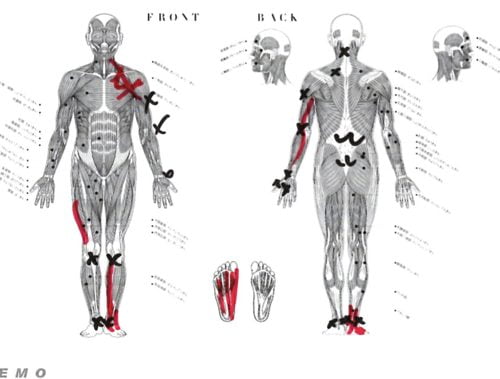

実際にお身体の状態を触診して確認してみるとこんな感じでした。

赤い線は筋肉や腱の硬直やヨジレ

Xは痛み ✔は痺れの場所

以前にヘルニアの手術後に歩けなくなってしまった女性の状態と似ていて膝から足の先、そして膝から鼠径部に向けて筋肉や腱・靭帯の硬直やヨジレがありました。

特にクルブシ付近と足裏のヨジレが大きくそこが足の指に力が入らない原因でした。

これらの硬直やヨジレはレントゲンやMRIには写りません。